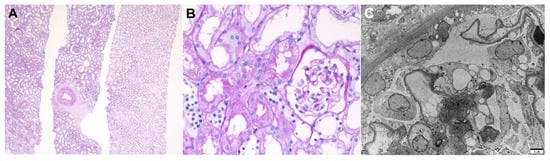

| Chronic thrombotic microangiopathy | 69/F | Acute kidney injury | Type 2 diabetes mellitus | Vector/ AstraZeneca (Cambridge, UK)/ 1st | 2/14 | LM: diffuse thickening of the capillary wall with capillary loop doubling, hyaline thrombi in glomeruli, intact tubules and interstitium, mild infiltration of lymphocytes in the interstitium, arterial fibrointimal thickening IF: fibrinogen 3+ in the glomeruli EM: duplications of the glomerular basement membranes with cellular interpositions, endothelial swelling and hypertrophy with occlusion of the lumens, glomerular intracapillary fibrin deposition with entrapped cellular debris, diffuse foot process loss | 0.80 at 1 year before biopsy | 3.69 | 5.20 | None | SR (21 weeks) |